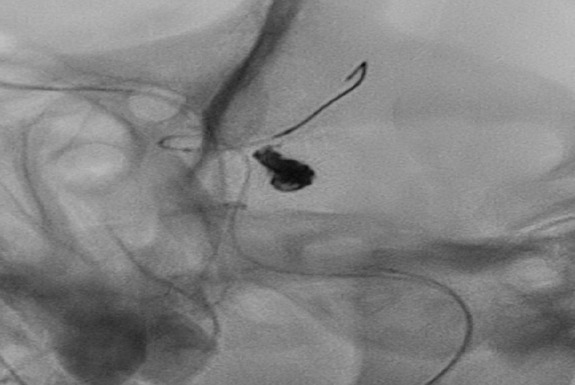

അമല ഇൻസ്റ്റിറ്റ്യൂട്ട് ഓഫ് മെഡിക്കൽ സയൻസസിൽത്രിശ്ശൂരിൽആദ്യമായി ബലൂൺ-അസിസ്റ്റഡ് കോയിൽ എംബൊലൈസേഷൻ വഴി പൊട്ടിയ ബ്രെയിൻ ആന്യുറിസം വിജയകരമായി ചികിത്സിച്ചു.  ബ്രെയിൻ ആന്യുറിസം തലച്ചോറിലെ രക്തക്കുഴലിന്റെ ബലൂൺ പോലെ വീർപ്പുള്ള ദുർബലാവസ്ഥയാണ്. ഇത് പൊട്ടുമ്പോൾ സബാരക്‌നോയ്ഡ് ഹെമറേജ് ഉണ്ടാകുന്നുപെട്ടെന്ന് കടുത്ത തലവേദനബോധക്ഷയംമരണത്തിനോ സ്ഥിരമായ വൈകല്യത്തിനോ ഇടവരുത്തുന്ന ഗുരുതരാവസ്ഥ.  പരമ്പരാഗതമായിഇതിന്    ക്രേനിയോട്ടമി ആവശ്യമായ തുറന്ന തലച്ചോർ ശസ്ത്രക്രിയയാണ് നടത്താറുള്ളത്. എന്നാൽഈ കേസിൽ കൈയിലോ അരയിലോ ചെറിയ ആർട്ടീരിയൽ പഞ്ചർ വഴി *എൻഡോവാസ്കുലാർ കീഹോൾ വഴി മൈക്രോകത്തീറ്ററുകൾ  ഉപയോഗിച്ച് ആന്യുറിസം വരെ എത്തിപ്ലാറ്റിനം കോയിലുകൾ സ്ഥാപിച്ച് അത് അടച്ചു. വിശാലമായ കഴുത്തുള്ള ആന്യുറിസത്തിൽ കോയിൽ സ്ഥിരമായി സ്ഥാപിക്കാൻ താൽക്കാലിക ബലൂൺ ഉപയോഗിച്ചു.  ഈ സാങ്കേതിക വിദ്യ തലയിൽ ശസ്ത്രക്രിയ മുറിവ് ഒഴിവാക്കുന്നുശസ്ത്രക്രിയാ ആഘാതം കുറയ്ക്കുന്നുവേഗത്തിൽ സുഖം പ്രാപിക്കാൻ സഹായിക്കുന്നു. രോഗി മികച്ച രീതിയിൽ സുഖം പ്രാപിച്ച്യാതൊരു പ്രവർത്തന ന്യൂറോളജിക്കൽ വൈകല്യങ്ങളുമില്ലാതെ ഡിസ്ചാർജ് ചെയ്യപ്പെട്ടു. ന്യൂറോ ഇന്റർവെൻഷണൽ വിദഗ്ധർ ഡോ. ജയശങ്കർ വി.ആർ.ഡോ. അരുണ്നാഥ് കെ.  അനസ്തീഷ്യ വിഭാഗം ഡോ. ജോൺ ഫ്രാൻസിസ്ഡോ. ഷീതൽ ബേബി എന്നിവർ നത്വത്വം നൽകി  ത്രിശ്ശൂരിലെ അത്യധുനിക ന്യൂറോവാസ്കുലാർ ചികിത്സയിൽ വലിയ മുന്നേറ്റമായി ഈ വിജയം